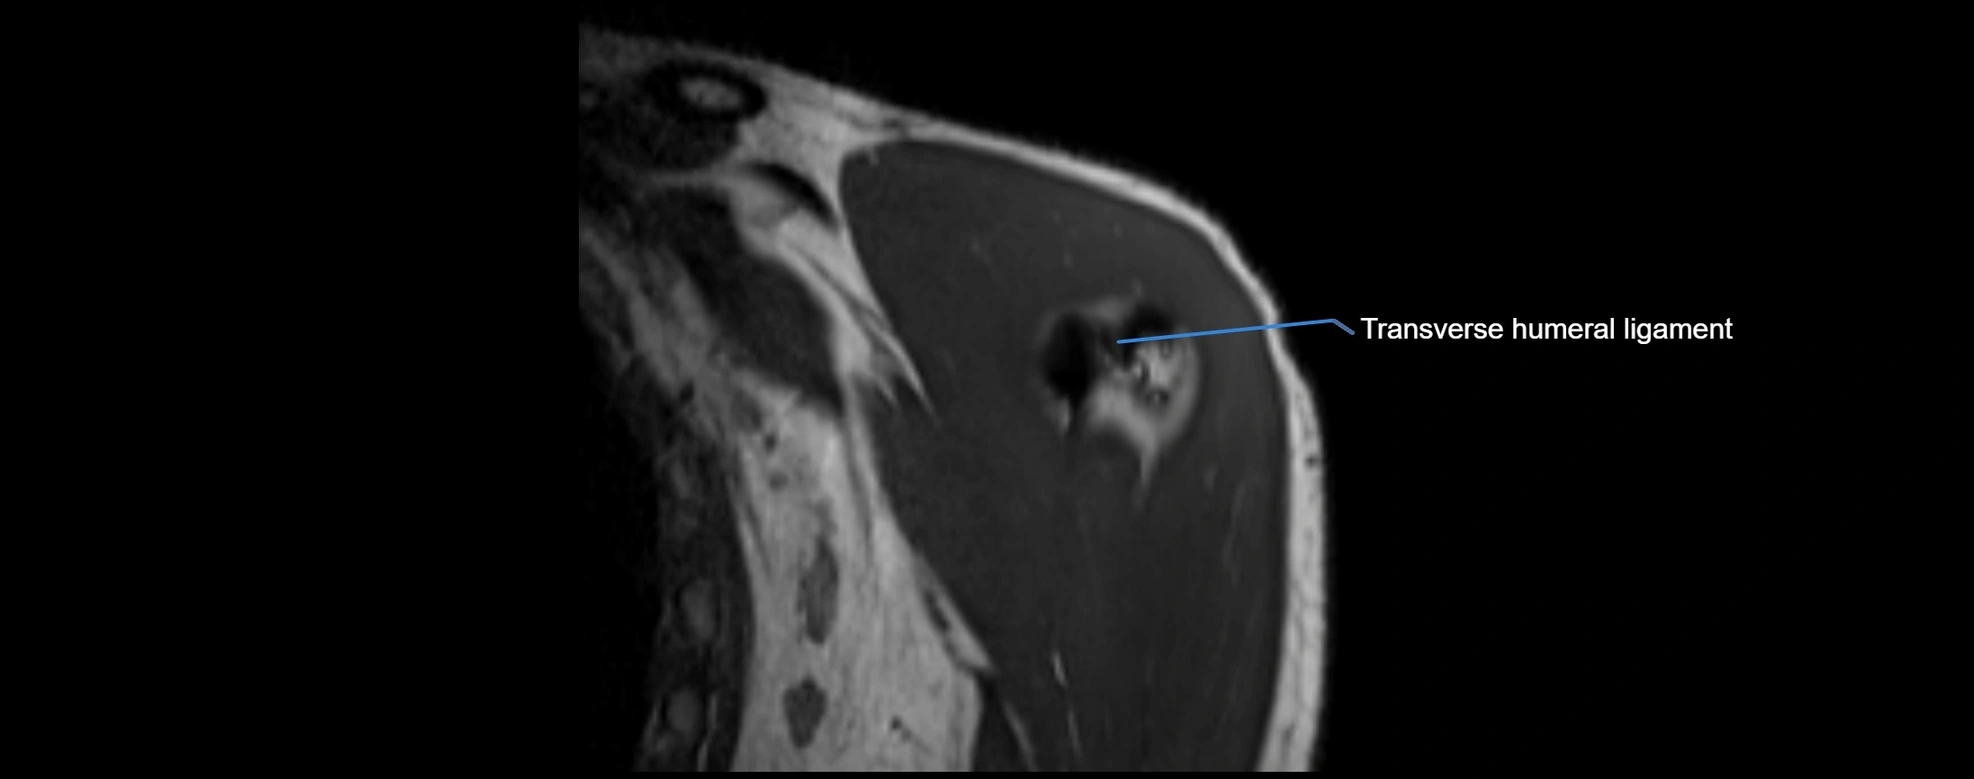

MRI Appearance

• T1-weighted images:

• Normal ligament: Low signal (dark linear band) spanning acromion to clavicle.

• Proton Density Fat-Saturated (PD FS):

• Normal ligament: Low signal, uniform thickness.

• Partial tear or sprain: Bright signal or contour irregularity.

• Complete tear: Clear discontinuity with bright signal gap and joint effusion.

• Excellent for assessing joint capsule, coracoclavicular ligaments, and periarticular edema.